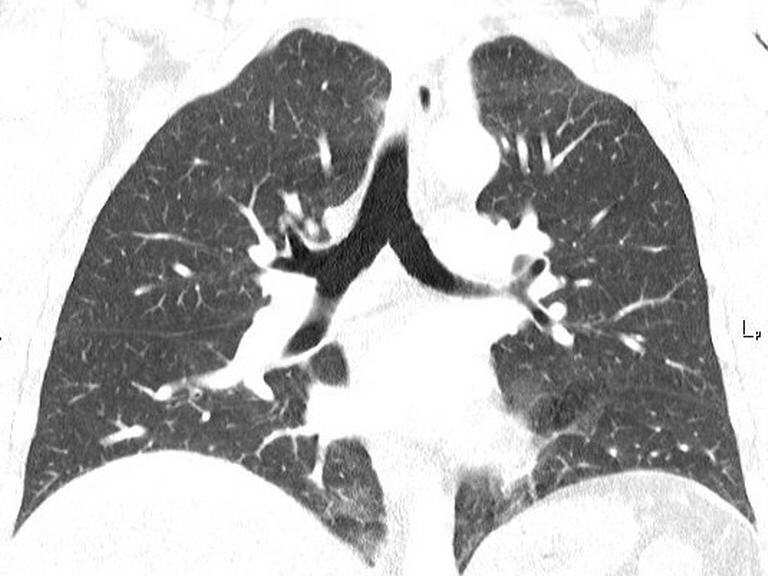

Die Computertomographie (CT) ist ein bildgebendes Verfahren, bei dem mithilfe von Röntgenstrahlen detaillierte Querschnittsbilder des Körpers erstellt werden. Der Patient liegt dabei auf einer Liege, die langsam durch einen ringförmigen Scanner fährt. Die CT erzeugt präzise Bilder von Organen, Knochen und Gewebe, die Ärzten helfen, Krankheiten oder Verletzungen genau zu diagnostizieren. Der Vorgang ist schmerzfrei und dauert in der Regel nur wenige Minuten. In manchen Fällen wird ein Kontrastmittel verwendet, um bestimmte Bereiche besser sichtbar zu machen.

- Lungen- und Abdomendiagnostik